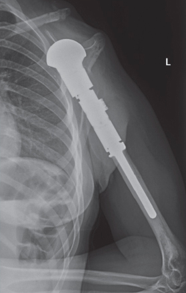

This is an x-ray image of the proximal humerus with the endoprosthesis fully inserted.